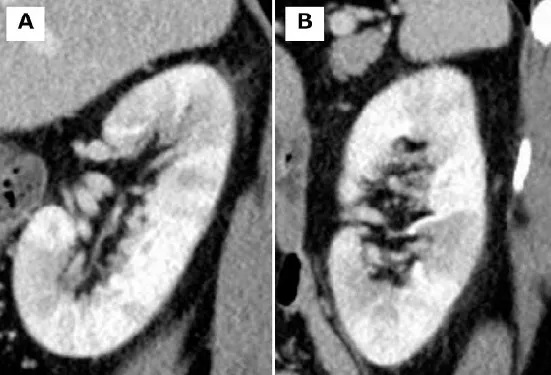

Diante de pacientes com múltiplos tumores de células renais claras devemos pensar na possibilidade de doença de Von-Hippel Lindau. O tratamento visando poupar massa renal pode fazer muita diferença

Valkercyo Feitosa

3 anos atrás